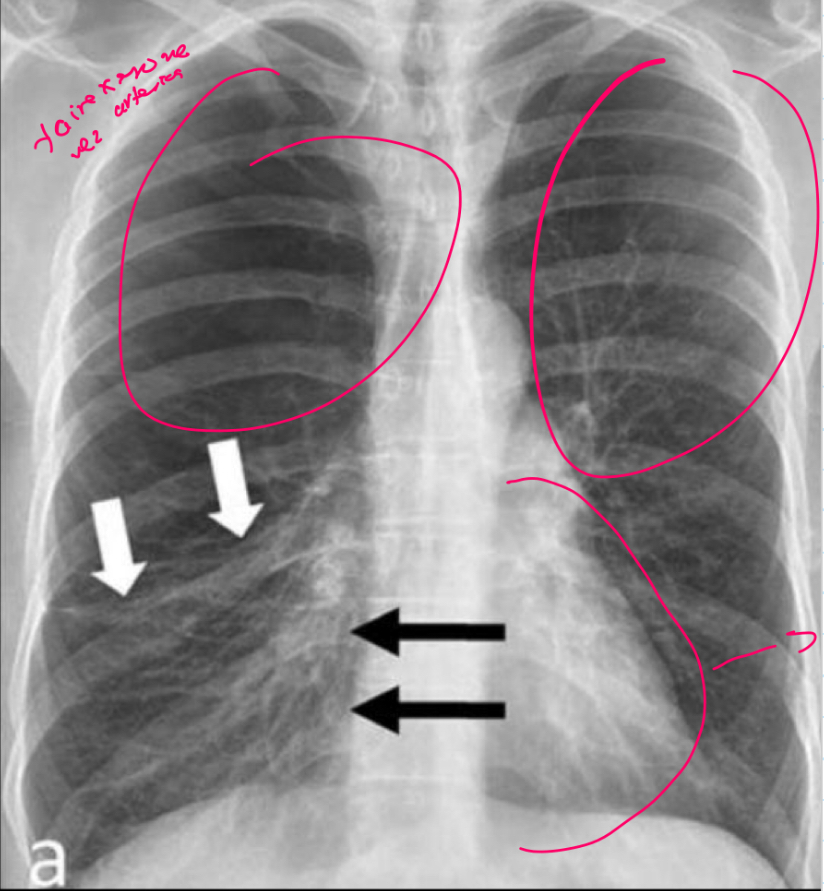

Q

Que es y como sabes

A

RX de enfisema x q hay hiperlucidez pulmonar

Se señala el corazón en GOTA